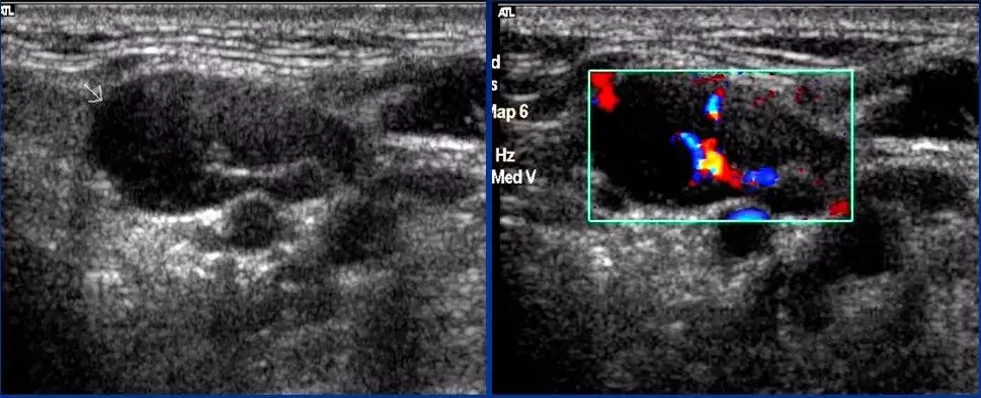

淋巴瘤

● 淋巴结不同程度肿大,多发,呈椭圆形、圆形,纵横比<2。

● 被膜清晰或不清晰,淋巴结之间可见融合。

● 皮质明显增厚呈低回声,不均匀,无液化、钙化;特征性回声改变为淋巴结内回声近似无回声的极低回声。

● 髓质变形或显示不清,或消失。

● 淋巴结内血流信号轻度或明显增多,分布杂乱;典型血流改变为淋巴结内血流信号丰富,红、蓝色血流信号充满整个淋巴结。

● 动脉血流速度加快,阻力指数正常或偏高。

淋巴瘤的血流信号在所有淋巴结中最为丰富。

淋巴结的内部回声一般表现为较均匀的低回声,当发生坏死时,其内部回声可相当低,接近无回声。